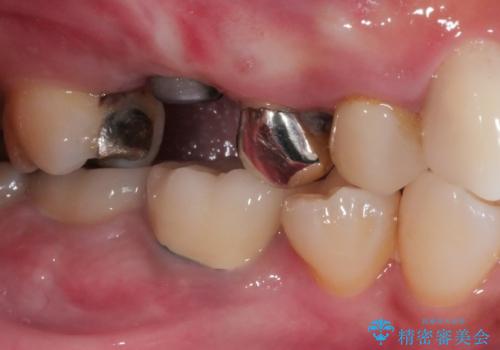

- 奥歯で噛んだ時の違和感を主訴に来院された患者様です。

歯根の先端の病変が大きく割れてしまっていた為、抜歯の必要がありました。

レントゲン等、検査を行ったところ骨の厚みは問題ないですが、

高さは少し低かったので、幅が太い短いインプラントを使って治療を行う計画を立てました。